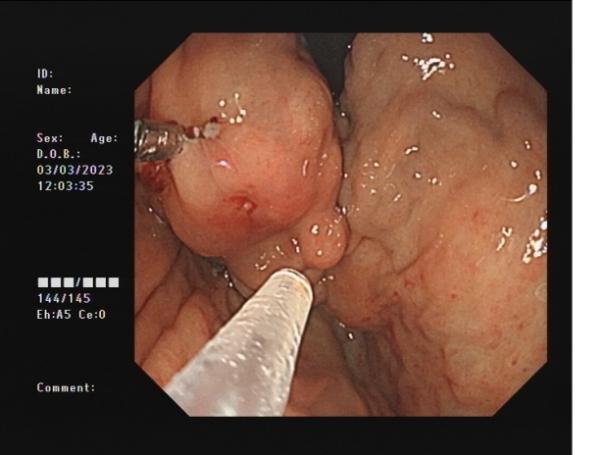

50f14f57e31f4fcb8cc67db07e7637a3.Jpeg5a155f6b9d364f049bf504276762fa4e.Jpegae69de3d0b564c66bdf2294699da75a6.Jpeg

胃底間質(zhì)瘤                內(nèi)鏡下全層切除術(shù)后創(chuàng)面         切除后標(biāo)本

內(nèi)鏡下全層切除術(shù)(EFTR):治療消化道黏膜下腫瘤(最主要):起源于固有肌層深層、部分腔外生長(zhǎng)、與漿膜層密不可分;少部分抬舉征陰性消化道癌前病變和早期癌;少部分困難解剖部位結(jié)腸病變(如結(jié)腸憩室內(nèi)腺瘤)等。